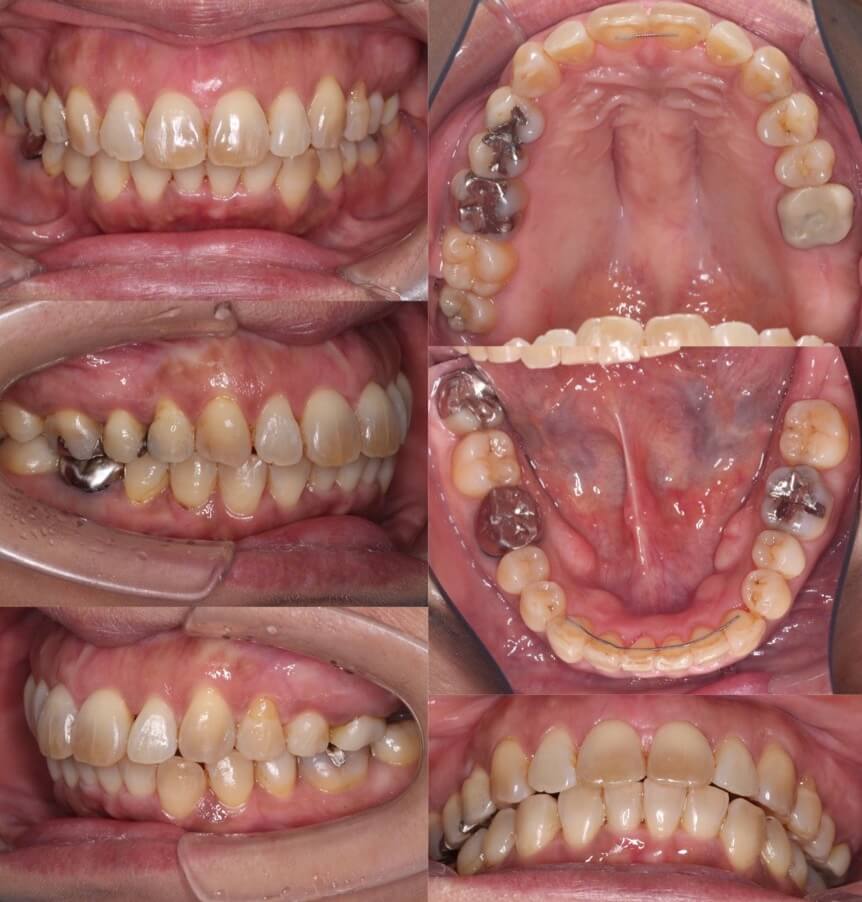

46歳女性・唇側矯正装置・抜歯

<症例概要>

主訴:前歯と口元の突出

年齢・性別:43歳女性

住まい:千葉県佐倉市

症状:叢生・上下顎前歯唇側傾斜

治療方針:上左右5番・下左右4番(計4本)

治療装置:唇側矯正装置

固定装置:ナンスホールディングアーチ

治療期間:3年

リテーナー:下フィックス+上下クリアタイプ

治療費用:968,000(税込)

代表的副作用:痛み・治療後の後戻り・歯根吸収・歯髄壊死・歯肉退縮

▶︎その他の副作用

前歯の突出のため口が閉じづらいことを気にされていて矯正治療を希望された患者さんです。年齢的に抜歯を行うか迷ったのですが、患者さんの主訴を優先して抜歯矯正により前歯を後方移動させました。抜歯部位については、上の歯並びは治療歯である第二小臼歯(5番)を選択しています。その分、治療期間は3年を超えてしまったのですが、理想的な横顔になりました。